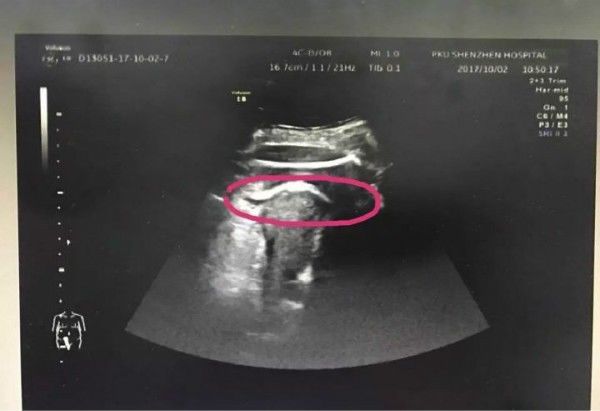

医生初步怀疑患者子宫破裂,当即安排做了B超。检查发现,胎儿的一条腿“踢破”了子宫,进入了腹腔,大腿根正卡在子宫壁上!

▲红色圆圈处是胎儿的腿,已经伸到子宫壁外